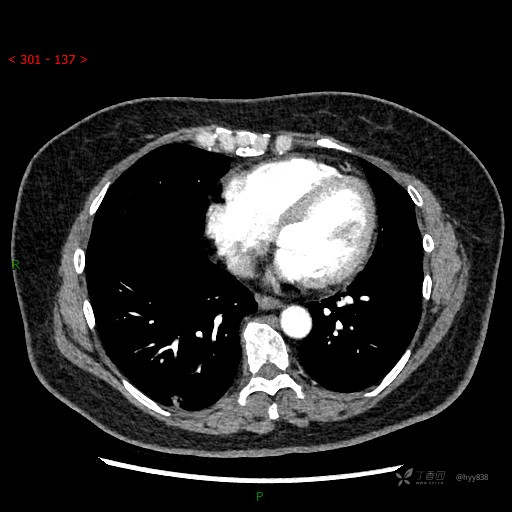

静脉期